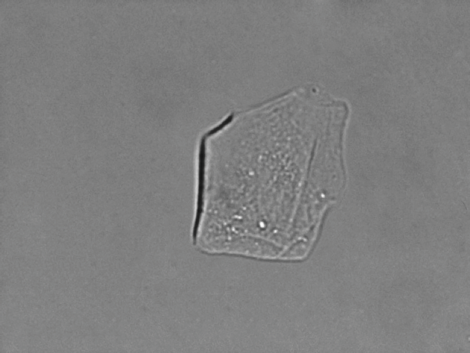

| 5. Cellules épithéliales malpighiennes |

Exemples d'images

Chaque analyse d’échantillon compte jusqu’à 96 images incluses, 6 d’entre elles étant automatiquement organisées pour que vous les examiniez. Vous pouvez également choisir librement les images à mettre en lumière ; elles sont toutes sauvegardées dans la base de données par un simple clic.

Toutes les images sont représentatives d’un champ de vision avec un objectif x40. Les images sont prises dans l’analyseur VETSCAN SA.

Cellules épithéliales malpighiennes